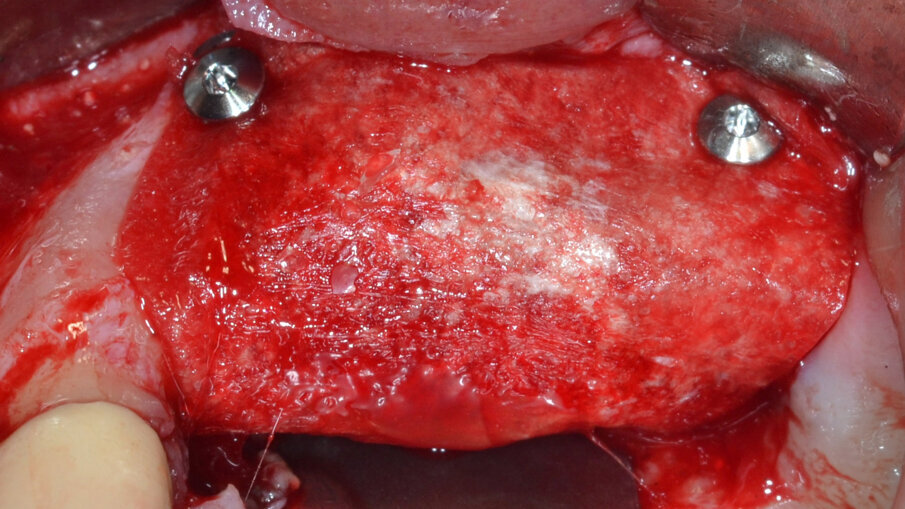

Dopo aver rimosso la protesi fissa e la relativa componentistica, vengono inserite due viti di copertura sterili per consentire una chiusura spontanea dei tessuti molli al fine di poter garantire una chiusura per prima intenzione e una guarigione della ferita chirurgica di tipo sommerso. La procedura chirurgica viene pianificata a distanza di 14 gg. Il primo tempo operatorio consiste nel disegno e nell’elevazione di un lembo di accesso a spessore totale delimitato da un’incisione crestale (effettuata all’ interno della banda di gengiva aderente) e da due incisioni di rilascio verticali leggermente divergenti tra loro (Fig. 3). Al sollevamento del lembo è possibile rilevare un notevole difetto intraosseo peri-implantare; sono inoltre presenti residui di biomateriale non integrato reliquati da un pregresso intervento di rigenerazione ossea (Fig. 4). Il tempo operatorio successivo consiste nel debridement del tessuto di granulazione e dei residui di biomateriale mediante un inserto a ultrasuoni (ES030ACT, Esacrom) (Fig. 5).

Fig. 3 - Elevazione di un lembo di accesso a spessore totale.

Fig. 4 - Presenza di un vasto difetto intraosseo peri-implantare con residui di biomateriale non integrato.